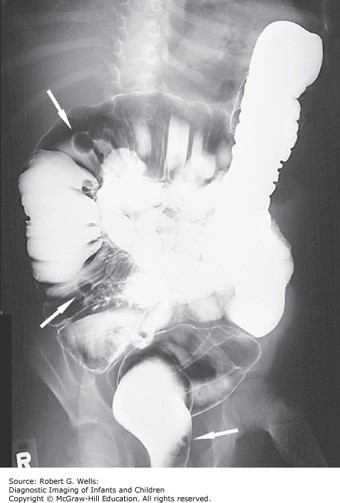

You recommend colonoscopy to better define the source of bleeding and find the following endoscopically:

B. Gardens of small, sessile polyps throughout the colon.

The correct answer is “B.” The most likely etiology is familial adenomatous polyposis (FAP) due to the significant colon cancer affecting family members at very young ages. FAP is an autosomal dominant condition that causes hundreds to thousands of colon polyps and eventual colon cancer if untreated. It is due to a mutation in a tumor suppressor gene (APC, adenomatous polyposis coli).